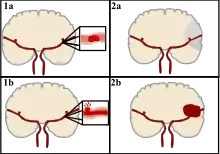

Stroke can be classified into two major categories: ischemic and hemorrhagic.[19] Ischemic stroke is caused by interruption of the blood supply to the brain, while hemorrhagic stroke results from the rupture of a blood vessel or an abnormal vascular structure. About 87% of stroke is ischemic, with the rest being hemorrhagic. Bleeding can develop inside areas of ischemia, a condition known as "hemorrhagic transformation." It is unknown how many cases of hemorrhagic stroke actually start as ischemic stroke.[2]

Ischemic

During ischemic stroke, blood supply to part of the brain is decreased, leading to dysfunction of the brain tissue in that area. There are four reasons why this might happen:

Hemorrhagic

There are two main types of hemorrhagic stroke:[29][30]

- Intracerebral hemorrhage, which is bleeding within the brain itself (when an artery in the brain bursts, flooding the surrounding tissue with blood), due to either intraparenchymal hemorrhage (bleeding within the brain tissue) or intraventricular hemorrhage (bleeding within the brain's ventricular system).

- Subarachnoid hemorrhage, which is bleeding that occurs outside of the brain tissue but still within the skull, and precisely between the arachnoid mater and pia mater (the delicate innermost layer of the three layers of the meninges that surround the brain).

Intracerebral hemorrhage

It generally occurs in small arteries or arterioles and is commonly due to hypertension,[52] intracranial vascular malformations (including cavernous angiomas or arteriovenous malformations), cerebral amyloid angiopathy, or infarcts into which secondary hemorrhage has occurred.[2] Other potential causes are trauma, bleeding disorders, amyloid angiopathy, illicit drug use (e.g., amphetamines or cocaine). The hematoma enlarges until pressure from surrounding tissue limits its growth, or until it decompresses by emptying into the ventricular system, CSF or the pial surface. A third of intracerebral bleed is into the brain's ventricles. ICH has a mortality rate of 44 percent after 30 days, higher than ischemic stroke or subarachnoid hemorrhage (which technically may also be classified as a type of stroke[2]).

Hemorrhagic stroke is classified based on their underlying pathology. Some causes of hemorrhagic stroke are hypertensive hemorrhage, ruptured aneurysm, ruptured AV fistula, transformation of prior ischemic infarction, and drug-induced bleeding.[66] They result in tissue injury by causing compression of tissue from an expanding hematoma or hematomas. In addition, the pressure may lead to a loss of blood supply to affected tissue with resulting infarction, and the blood released by brain hemorrhage appears to have direct toxic effects on brain tissue and vasculature.[46][67] Inflammation contributes to the secondary brain injury after hemorrhage.[67]